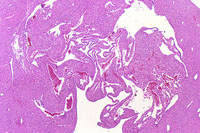

A hemangioma has destroyed the normal hepatic parenchyma. A thrombus is present at the top of the hemangioma; high magnification shows dilated vascular channels lined by flattened endothelial cells. There is minimal atrophy of hepatic cords.